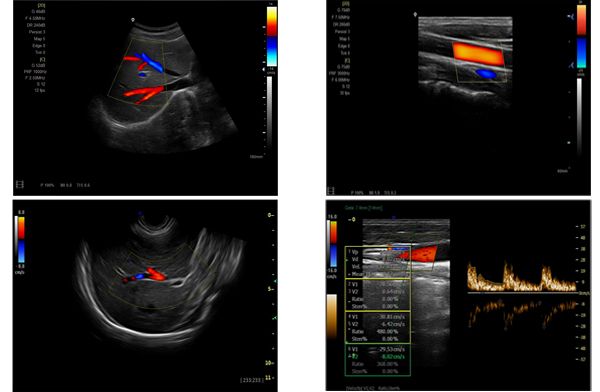

為高集成數(shù)字式彩色多普勒系列產品之一,廣泛實施于腹部,產科,婦科,血管,小器官,泌尿,新生兒和兒科等臨床,屬全身應用型彩色多普勒儀器。

●全身應用型包含2D/CFM/PDI/PW/ M等掃描模式;